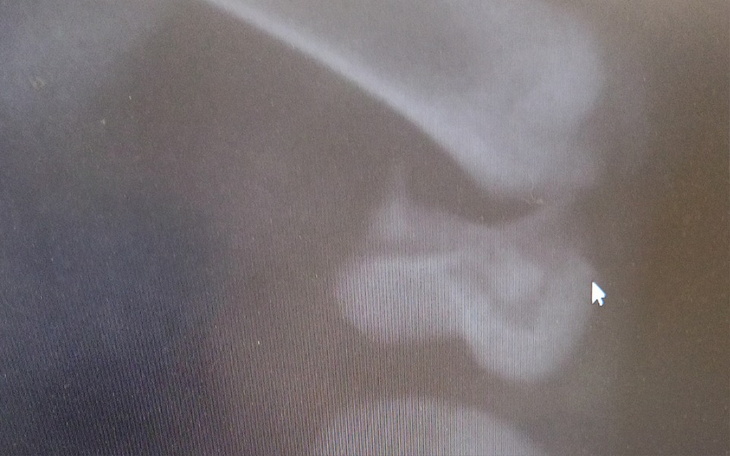

Ratunku ta mała Celinka potrzebuje wsparcia , musi przejść zabieg złożenia nóżki. Pojawiła się przyniesiona przez mieszkankę Wielunia. Siedziała cichutko pod kontenerem obok jedzenie nietknięte. Sprawdziliśmy monitoring i wiemy że dwa kotki bawiły się beztrosko na parkingu wchodziły w nadkola samochodów skąd przyszły nie wiemy ale los tej małe jest smutny bo niestety kierowca nie zauważył że maluchy są w nadkolu i ruszył jedna mała została wystrzelona z pod koła a druga prawdopodobnie pojechała dalej. Koteczka miała zrobione rtg i złamanie jest poważne . Bez operacji nóżka będzie krótsza o 1.5 cm. Bardzo was proszę o pomoc w zebraniu tej kwoty. Dajmy jej szansę na normalne życie.kazda wpłata zwiększa nasze szane. Dziękuję ❤️❤️❤️❤️❤️❤️❤️❤️❤️❤️❤️❤️❤️❤️❤️❤️❤️